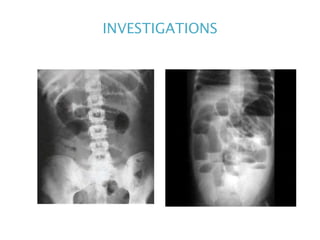

INVESTIGATIONS

Jejunum shows concertina effect due to valvulae

Triad of small bowel obstruction in plain

1. Dilated small bowel loops > 3 cm.

2. Multiple air fluid levels in erect x-ray.

3. Paucity of air in the colon.